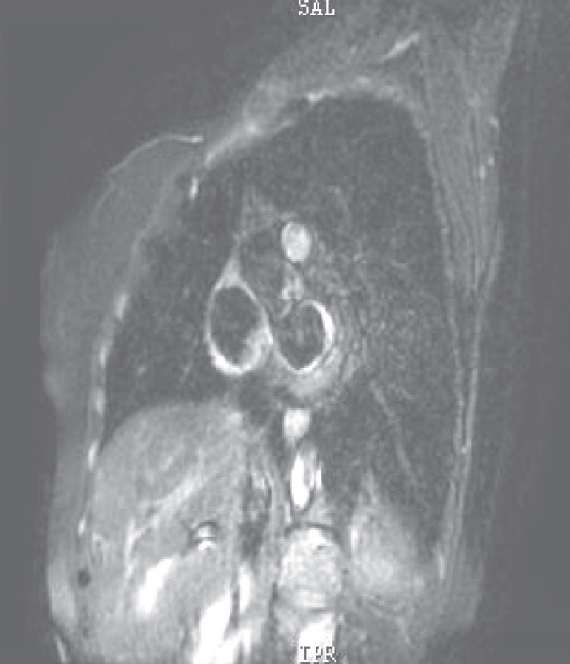

心脏MRI见心肌灌注均匀(图4)。

图4 心肌MRI结果